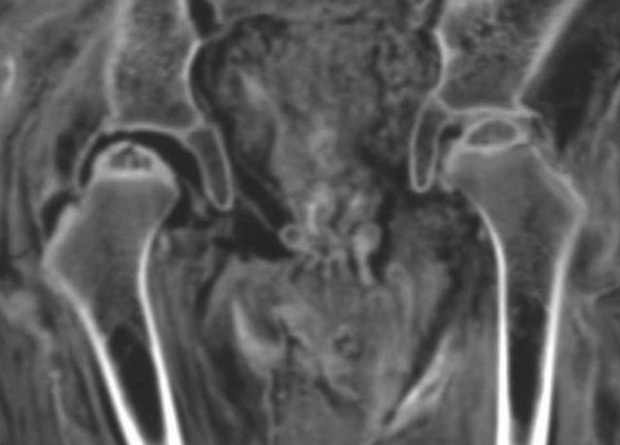

Палеопатологи исследовали с помощью компьютерной томографии 21 древнеегипетскую детскую мумию. Ученые определили пол и возраст на момент смерти большинства этих детей, а также обнаружили у трех индивидов свидетельства перенесенных гнойных инфекций: синусита, паратонзиллярного (или парафарингеального) абсцесса, целлюлита или абсцесса, а также септического артрита. Результаты исследования опубликованы в International Journal of Paleopathology.